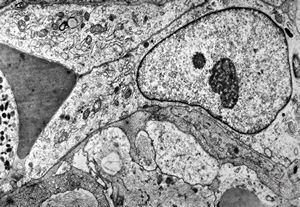

M,10y. | herpetic encephalitis